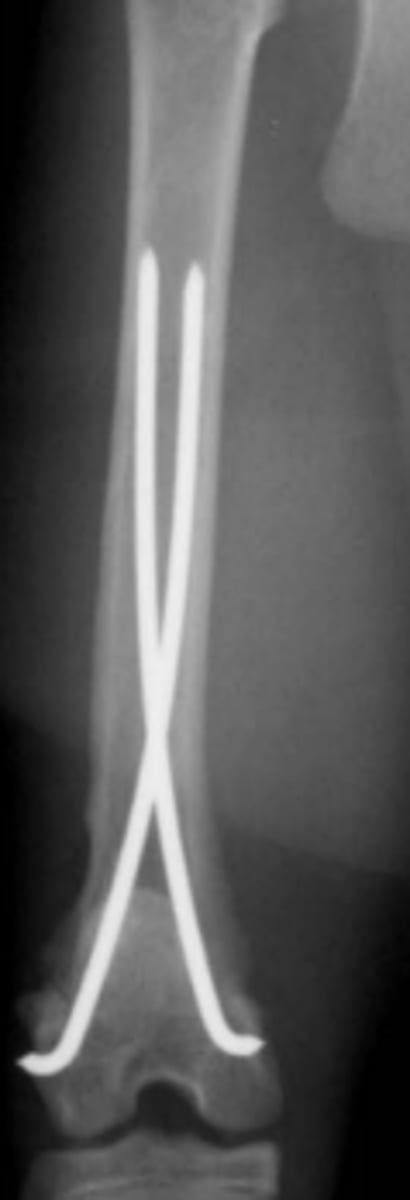

Rush pins

Jacob's chuck & key

Steinmann pin

Kirschner wire